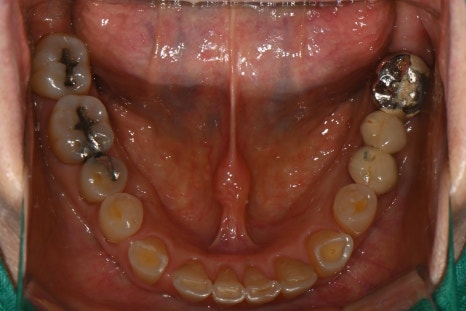

Panoramic X-ray immediately after surgery

This is the X-ray taken immediately after implant surgery.

During the osseointegration period, we checked the teeth on both sides for any irritation or discomfort, and the patient was advised to live with temporary prosthetics.